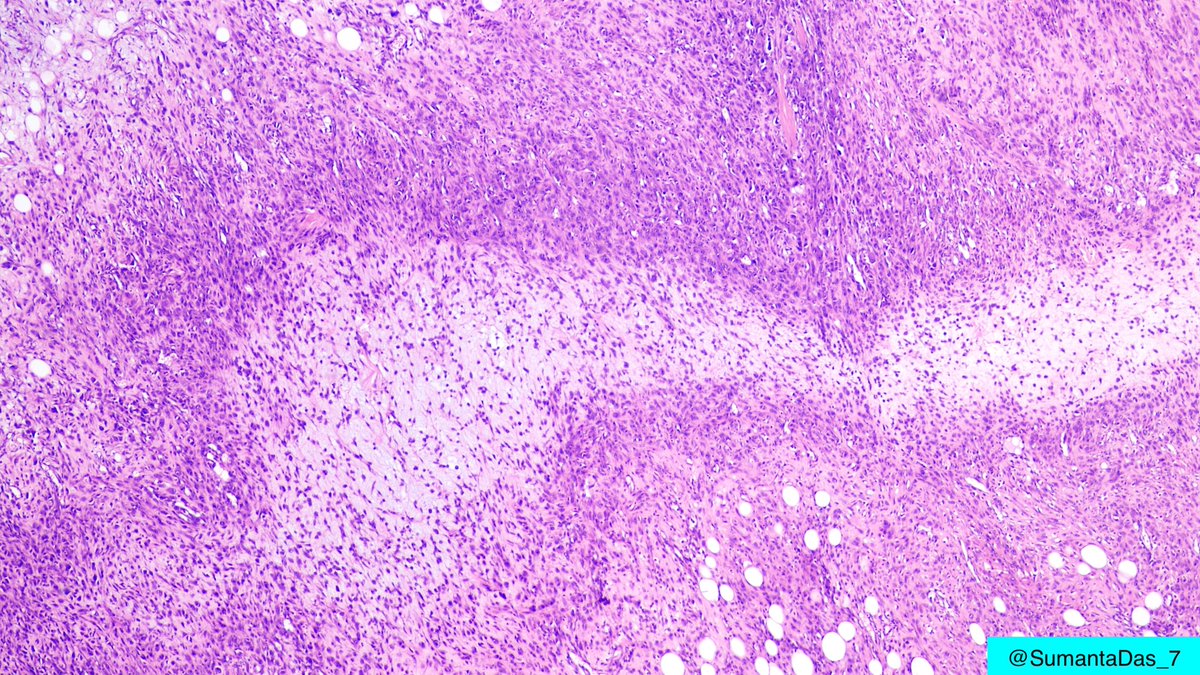

Male in 40s. Forearm mass. On low magnification, hypercellular area and hypocellular loose myxoid areas. On high magnification, sheets of ganglion-like cells with amphophilic cytoplasm, vesicular nuclei and prominent nucleoli. #PathTwitter #BSTpath

1

24

54